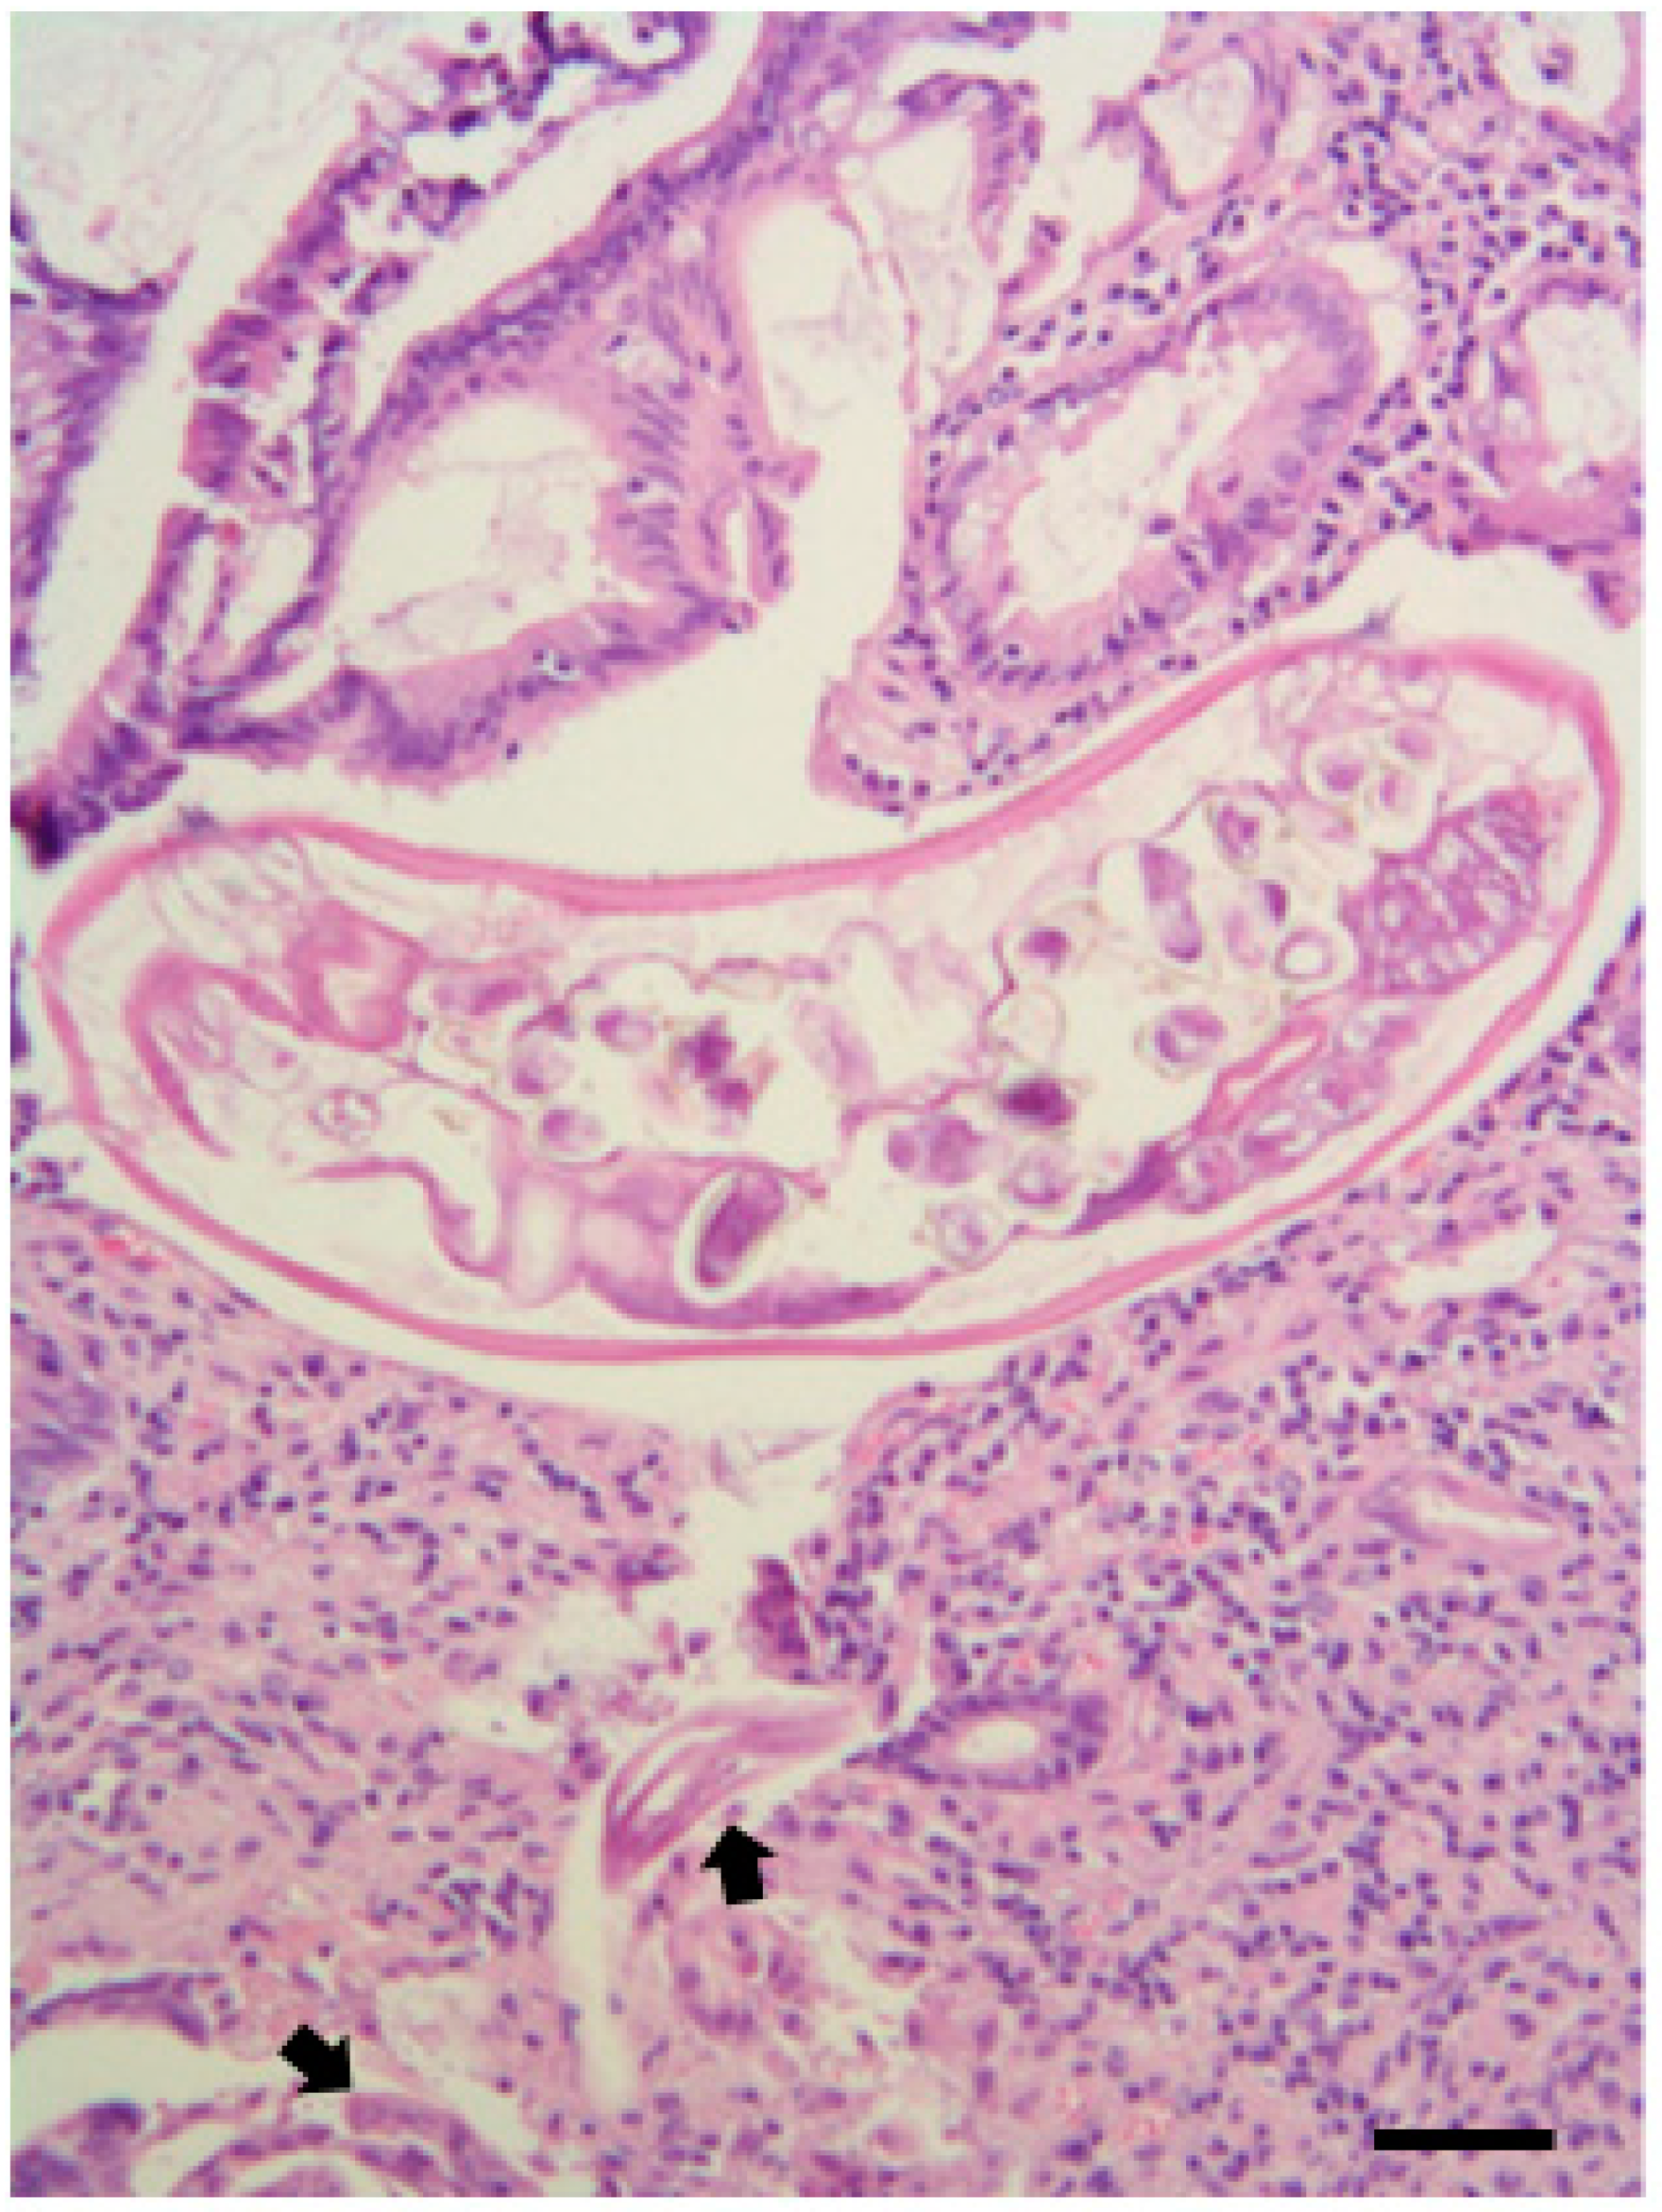

| Common buzzard 2 | Gizzard, Proventriculus, Intestine | Procyrnea mansioni (Nematoda: Habronematidae) 1 * Porrocaecum angusticolle (Nematoda: Ascarididae) 1 * Baruscacapillaria falconis (Nematoda: Capillariidae) 2 * Spirocerca spp. encysted larvae (Nematoda: Thelaziidae) 4 * | - | Neodiplostomum attenuatum (Platyhel-minthes: Diplostomatidae) 2 * | Centrorhynchus globocaudatus (Acanthocephala: Centrorhynchidae) 2 * | - |

| Common buzzard 3 | Esophagous, Gizzard, Proventriculus, Intestine | Eucoleus dispar (Nematoda: Capillariidae) 4 * Porrocaecum angusticolle (Nematoda: Ascarididae) 6 * Baruscacapillaria falconis (Nematoda: Capillariidae) 13 * Procyrnea mansioni (Nematoda: Habronematidae) 50 * | - | Neodiplostomum attenuatum (Platyhel-minthes: Diplostomatidae) 50 * | Centrorhynchus aluconis (Acanthocephala: Centrorhynchidae) 9 * | - |